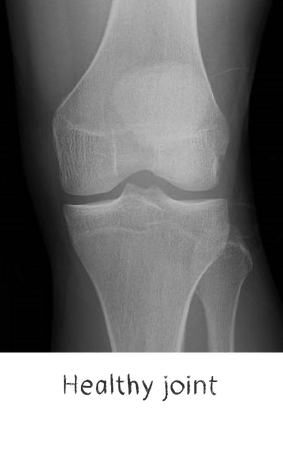

Plain film x-rays are taken to assess the joint

These are usually taken prior to your appointment. These help to confirm the diagnosis, assess the wear pattern and look for particular deformities. They can show old metalware and its position in the bone.